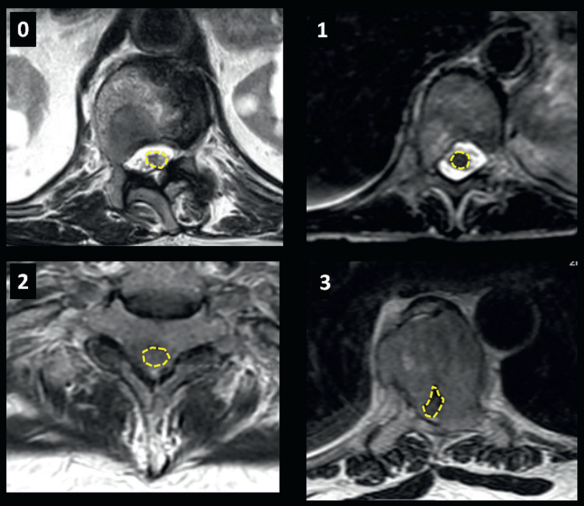

Bilsky và cộng sự đề xuất hệ thống phân loại chèn ép ủy thành thang điểm 4 và 6 mức độ. Trong đó thang điểm 4 mức độ được áp dụng rộng rãi hơn. (hình 1) Chèn ép tủy độ 2 và 3 được cân nhắc là cấp cứu trong ung thư.

Hình 1. Bốn mức độ chèn ép tủy theo Bilsky. Độ 0 – chỉ có tổn thương xương. Độ 1 – Tổn thương xâm lấn vào ngoài màng cứng, chạm đến màng tủy nhưng chưa chèn ép tủy. Độ 2 – Xâm lấn vào ngoài màng cứng có chèn ép tủy nhưng chưa xóa khoang dịch não tủy. Độ 3 – Chèn ép tủy gây biến dạng tủy sống, xóa khoang dịch não tủy.